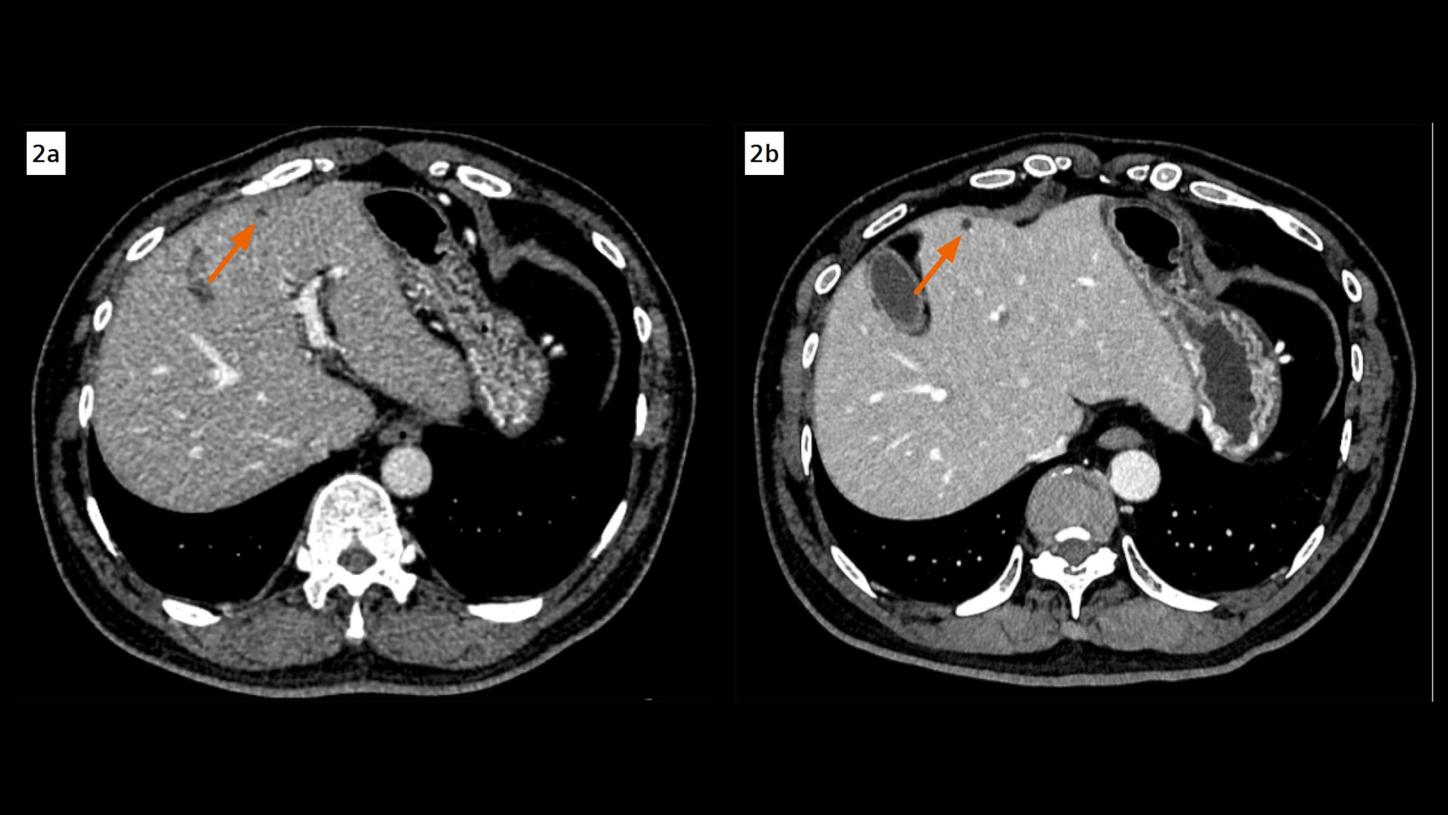

Fig. 2:A hypoattenuating lesion in the hepatic segment IV, exhibiting indistinct margins and equivocal enhancement in an EID CT image (Fig. 2a, arrow), is clearly characterized as a non-enhancing, sharply delineated cyst in a PCD CT image (Fig. 2b, arrow). Both images are reconstructed at 1 mm, displayed at same window settings. The image noise is notably less in the PCD CT image.